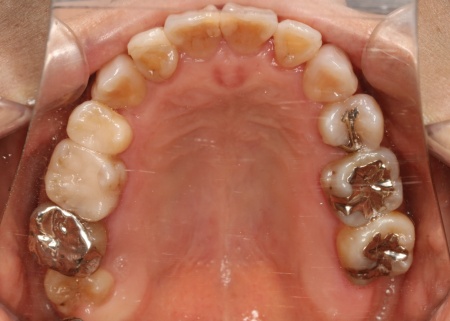

治療前

診断結果 拝見したところ、上下の歯がデコボコに乱れて生えていました。

歯の大きさに対して顎が小さいため、歯が正常に並びきらず、全体的な噛み合わせのバランスも崩れています。

噛み合わせを詳しく検査したところ、実際にしっかりと噛み合っているのは一部の歯だけで、このまま放置すると特定の歯に負担が集中し、将来的に痛みや違和感が生じるおそれがあります。

また、銀歯が装着されている右下奥歯は以前神経を抜く治療がされていましたが、現在は歯の具合が良好とはいえず、温存が難しい状態です。